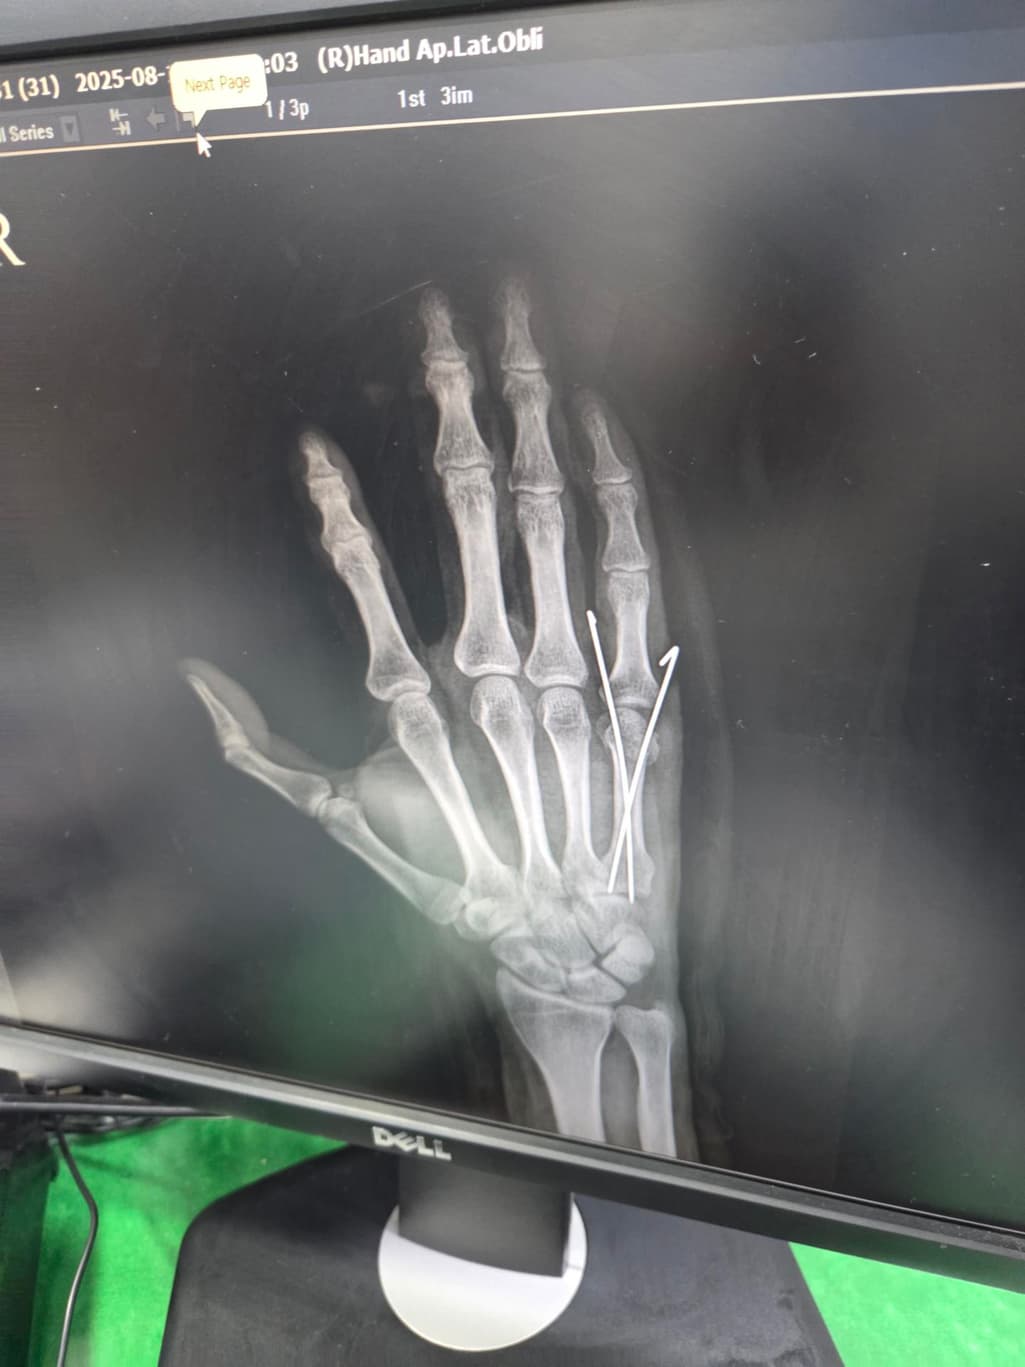

중수골 골절 수술 잘된건지 봐주세요?

수술 직후 사진이고요

두 번째 사진을 보시면 수술한 손가락이 다른 손가락에 비해 뼈가 잘 정렬이 안 된 것 같아서요. 수술적으로 잘못된 부분이 있는지 알려주시면 감사하겠습니다.

엑스레이상으로는 금속 핀을 박은 수술로 보이며 사진상 정확한 상태 확인이 어렵긴 하지만 크게 정렬이 틀어지거나 문제는 없는 것으로 보입니다.

제가 직접적으로 수술의 판단해 드리긴 어렵습니다. 다만 사진상으로는 금속 핀 고정으로 뼈 정렬을 잡은 흔적이 보이며 수술 직후에는 약간의 틀어짐이 있어도 시간이 지나면서 유합과정에서 교정되는 경우가 많습니다.뼈가 완벽히 일직선으로 맞지 않아도 기능 회복에는 큰 지장이 없는 경우도 흔합니다!